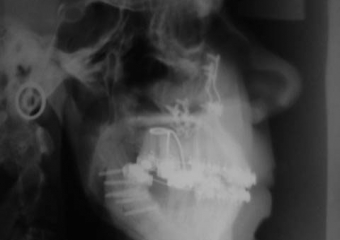

Telerradiografia inicial  - Clínica Cliniface

Telerradiografia inicial